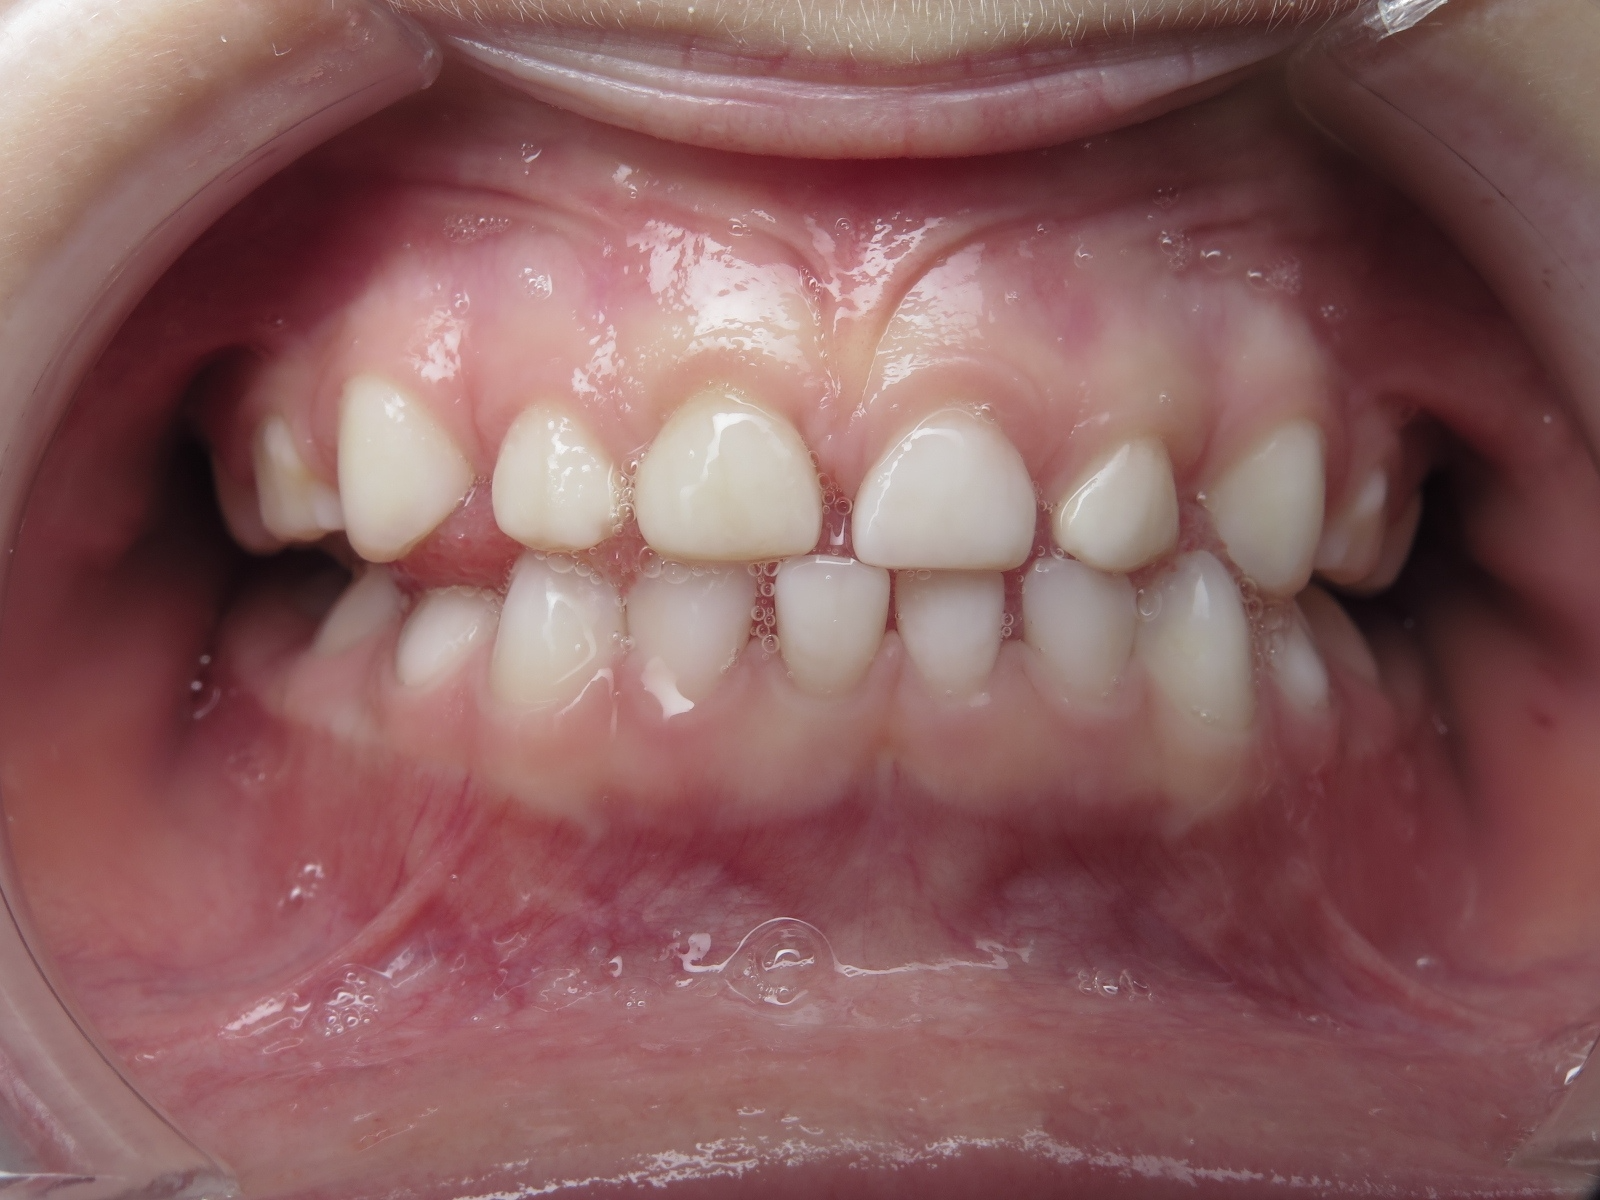

7.inversé droit 4 ans

inversion des dents postérieur coté droit

bilan début et en cours de traitement